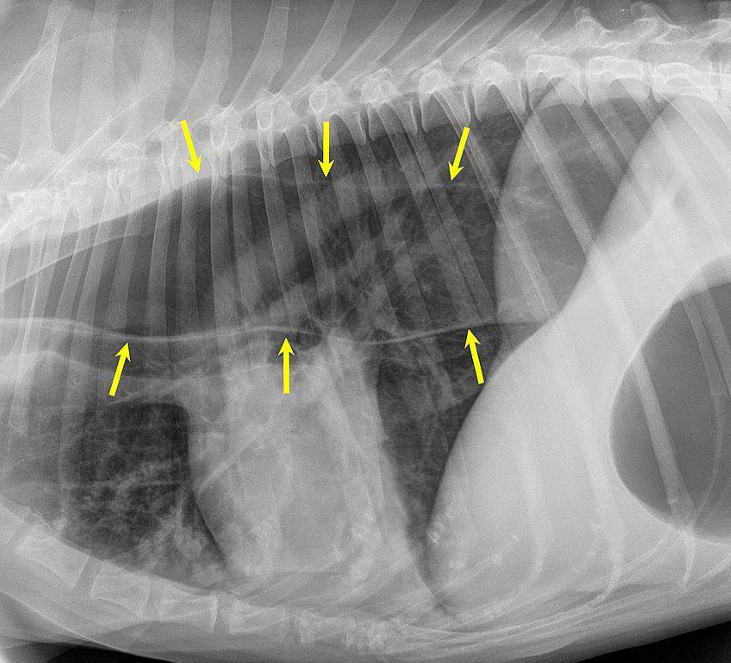

![]() | Megaesophagus - Mediastinum에서 만날 수 있는 변화 - 생각보다 흔함 - 거대식도+호흡기 증상 ⇒ 오연성 폐렴 동반. |